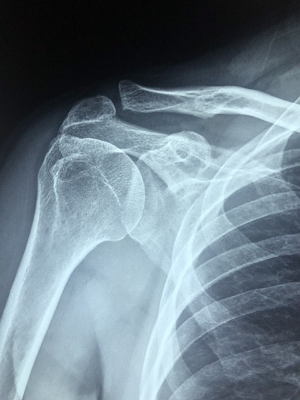

👉 소변 검사 + CT, X-ray 필요